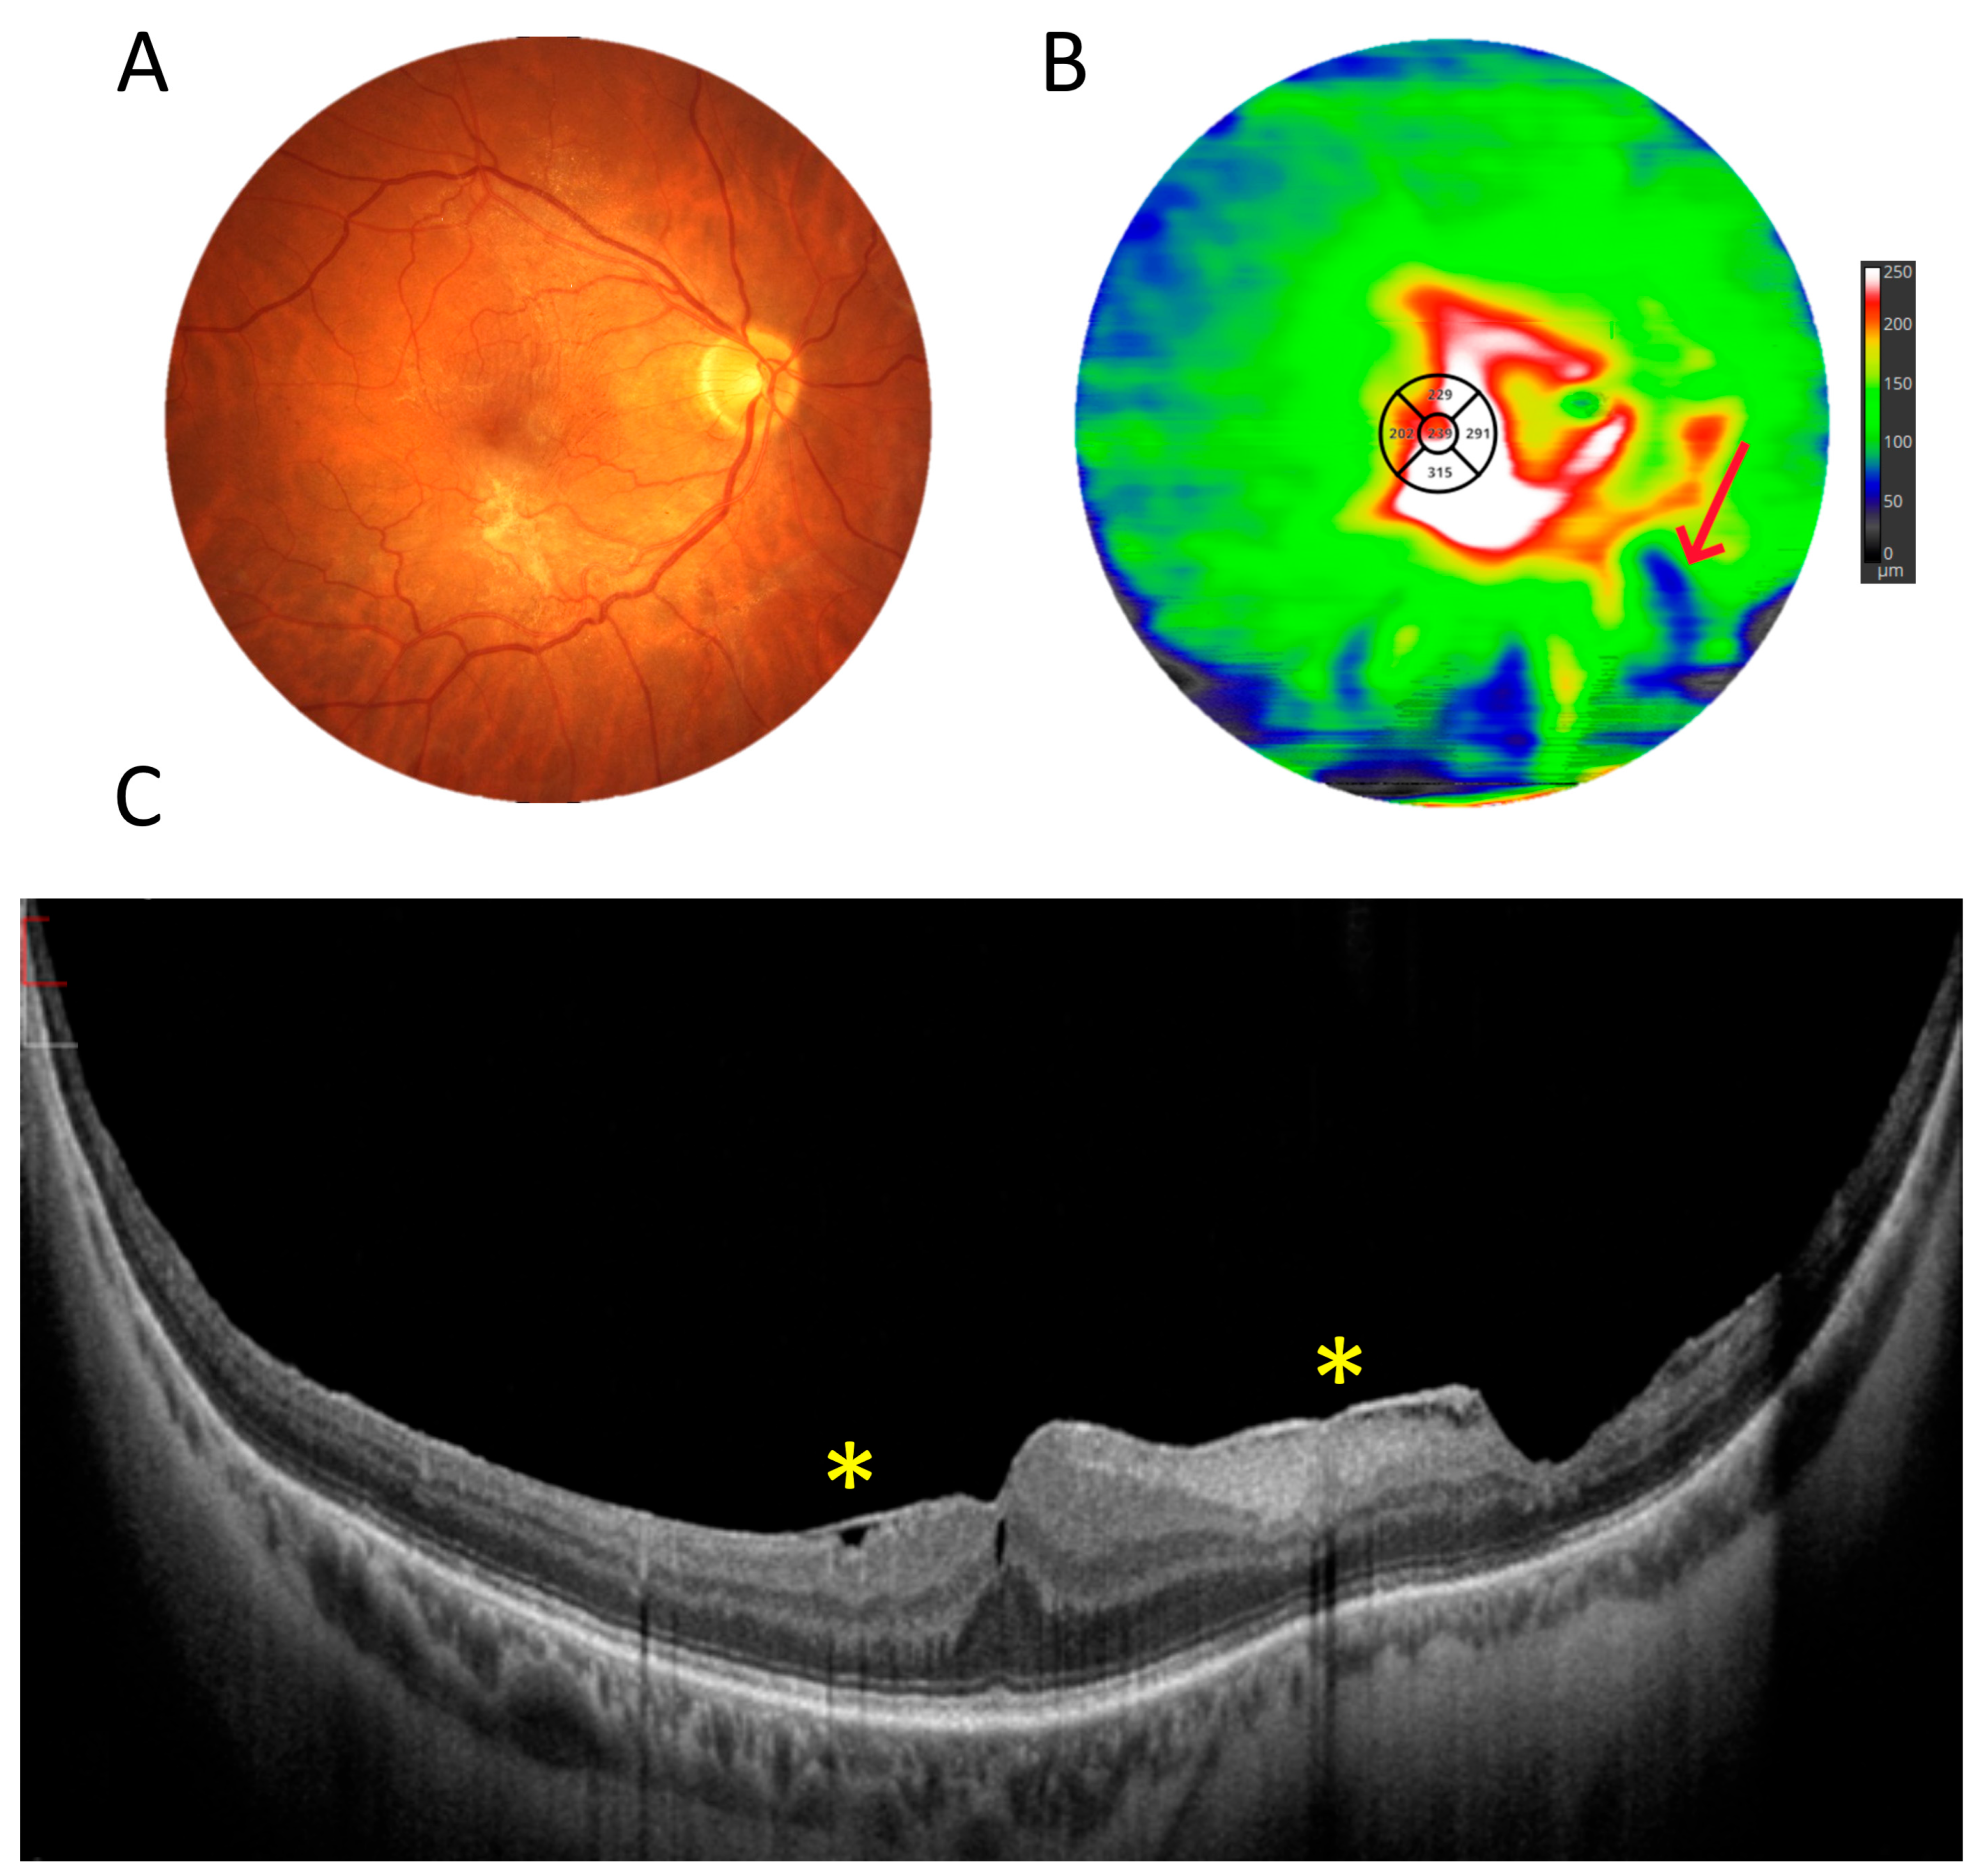

3.5. Retinal Thickness Measurements

4. Discussion